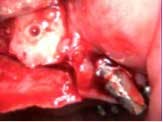

A 53-year-old female with a medical history of hypothyroidism, seasonal allergies, and asthma taking Synthroid and Singula presented to my office with pain in No. 3, failed root canal therapy, and a fracture. The tooth was deemed hopeless and extraction and implant placement was treatment planned. Under local anesthesia, tooth No. 3 was sectioned into three pieces and extracted. The sockets were debrided, filled with gel foam, and closed with chromic gut sutures. Healing was uneventful. The patient did not return for two years for follow-up. A CT scan was taken, which confirmed that approximately5 mm of bone remained below the floor of the sinus. After reviewing the options with the patient, a treatment plan of an internal sinus lift (osteotome), bone graft, platelet-rich fibrin (PRF) and simultaneous implant placement was agreed upon. Under local anesthesia, a full thickness flap with two vertical releasing incisions was performed at tooth No. 3 site. A trephine bur was used to a depth of 4 mm. An osteotome was then employed to infracture the bone core, which remained attached to the Schneiderman membrane. A bone graft consisting of DFDBA, anorganic bovine bone, and PRF was used in the osteotomy to increase the vertical bone height using sequential osteotomes. After sufficient elevation, a 7x9 tapered implant was placed on low speed to 50% of the implant depth. The remaining placement of implant was done with a hand torque on 50 ncm to allow for further expansion of the alveolar housing. A healing abutment was placed using the principles of platform switching. Healing was uneventful, and integration was successful.

Case 1: Implant and osteotome bone graft through the socket with Southern Implant